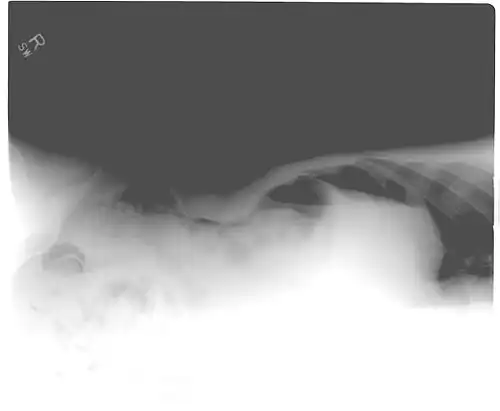

Pneumoperitoneum seen on X-ray with the patient lying on his left side. -